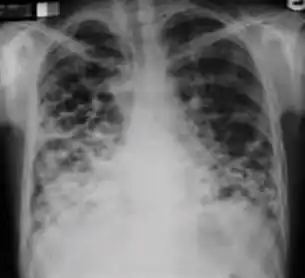

7. Other - Any other finding suggestive of active TB, such as miliary TB. Miliary findings are nodules of millet size (1 to 2 millimeters) distributed throughout the parenchyma.